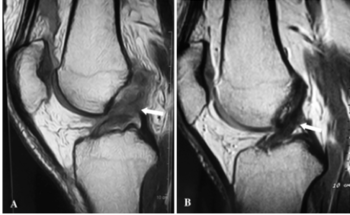

This documentary also highlights that it is possible to manage a knee ligament injury without surgery. There is emerging evidence that both ACL and PCL injuries can be managed without surgery and allow for people to return to their pre-injury level of sport (4, 5). This is due to many factors, one of the major reasons being that there are cases where a torn ligament has the potential to spontaneously heal, just like in Connors case. Multiple magnetic resonance imaging (MRI) studies have demonstrated that partially and fully torn ACL’s can reattach with time and conservative (non-surgical) care (5, 6) (Figure 2).